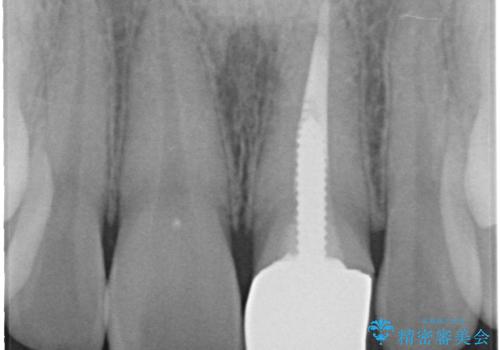

- 以前装着された前歯のかぶせ物の色を変えたいとのことで来院されました。

土台からの再治療を行い、オールセラミッククラウンを装着する治療計画としました。